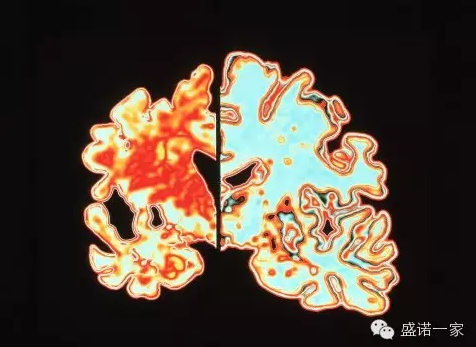

阿尔兹海默病是一种慢性进行性的疾病,所以疾病在诊断明确之前,往往已经平均存在8年之久。阿尔兹海默症患者脑区域内有大量的淀粉样蛋白沉积和神经纤维缠结,它们被认为是造成神经元损伤的主要原因。正因为这种显著的淀粉样蛋白沉积和神经纤维缠结,阿尔兹海默症被认为是一种蛋白质异常聚集造成的疾病,主要是由大脑中异常切割产生的Aβ或tau蛋白大量积累造成的。神经细胞膜上有一种跨膜蛋白叫做淀粉样前体蛋白(APP),它对神经元生长、存活和创伤后修复有着关键性作用。在阿尔兹海默症病人中,病变导致APP被酶分解成小分子片段——其中之一就是Aβ,它会在神经元外部大量积累和沉积,造成神经元的衰亡。

同时随着时间的流逝,阿尔兹海默症患者的大脑会持续萎缩,记忆、思维和计划能力全部丧失;形成新记忆的海马体也收缩,直接导致新的事情记不住;脑室扩大,大脑积液变多。这些变化,造成的后果最终波及全身。